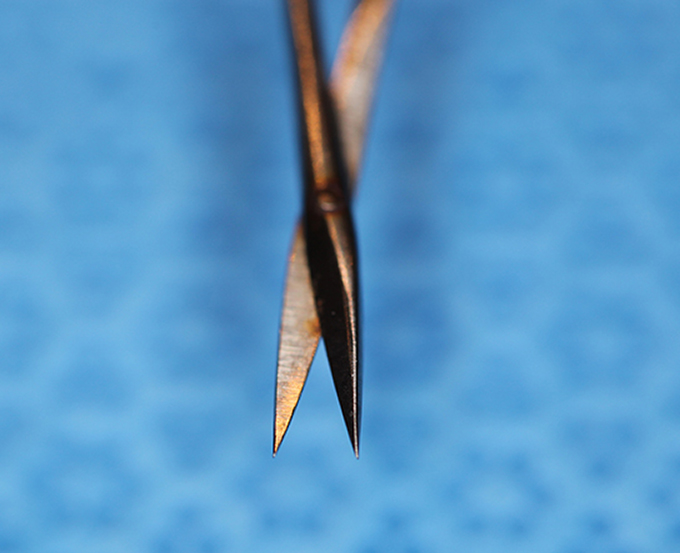

Scissor, Stevens tenotomy curved

Stevens

Catalog: Storz E3562

Typical Use(s): Dissection into quadrants

Scissor, Stevens tenotomy curved (Enlarged)

Stevens

Catalog: Storz E3562

Typical Use(s): Dissection into quadrants

Scissor, Stevens tenotomy curved (Curved Close-up)

Stevens

Catalog: Storz E3562

Typical Use(s): Dissection into quadrants